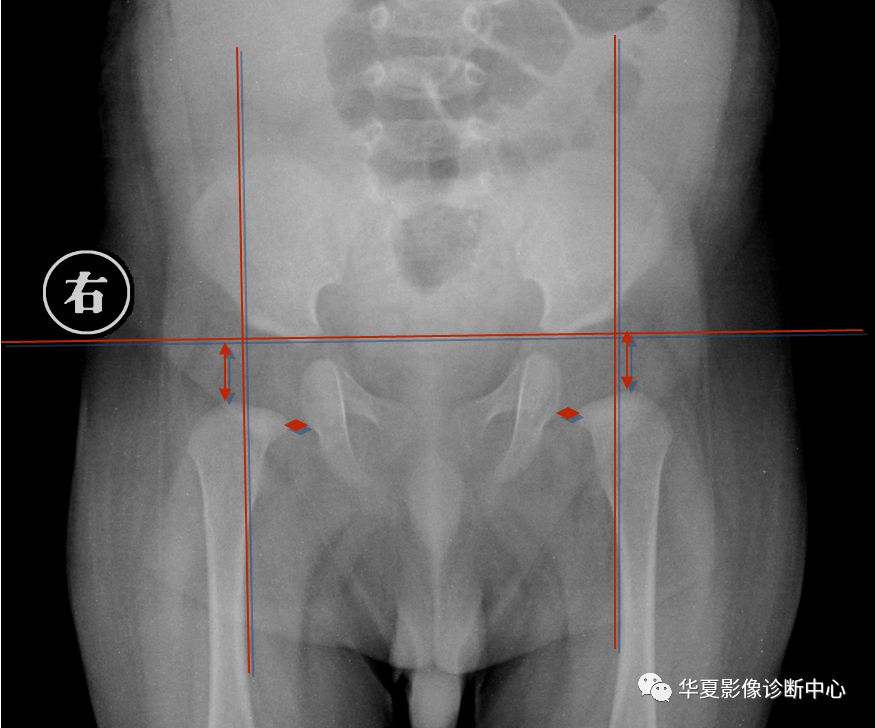

2.骨盆平片测量法

如图所示两侧髋臼Y形软骨连成为Hilg-eneriner线,简称为H线,股骨上端距H线之距离为上方间隙。股骨上端鸟嘴距坐骨支外缘为内侧间隙,正常均值上方间隙为9.5mm,内侧间隙为4.3mm。若上方间隙小于8.5mm,内侧间隙大于5.1mm应怀疑髋关节脱位。若上方间隙小于7.5mm,内侧间隙大于6.1mm可诊断为髋关节脱位,此法简易可靠。